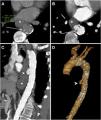

Si la sospecha es de erosión del injerto en contexto de FAE secundaria, las técnicas de medicina nuclear como 18-FDG PET-TC o SPECT con leucocitos marcados pueden ser de gran utilidad para detectar la presencia de infección periinjerto22 (fig. 9). Demostrar la existencia de fistulización en ausencia de signos específicos es un verdadero reto diagnóstico, ya que los hallazgos de infección se superponen con los de la FAE. Es precisamente en estos casos donde la gammagrafía con hematíes podría ser de utilidad.

Erosión del injerto en varón de 61 años con antecedente de bypass aortobifemoral que presenta fiebre de largo tiempo de evolución, escalofríos, debilidad y bacteriemia persistente. Ante la sospecha de infección del injerto se realiza TC con CIV en fase portal (A, B, C) que revela edema periinjerto y engrosamiento parietal de la tercera porción del duodeno (*) englobando la rama iliaca derecha del bypass en ausencia de plano graso de separación. La reconstrucción sagital (D) representa el nivel de los cortes axiales y la reconstrucción coronal (E) apoya los hallazgos descritos. No se objetiva extravasación de CIV. Se realiza SPECT con leucocitos marcados (F, G) que demuestra acúmulo de radiotrazador y PET-TC (H) que pone de manifiesto el incremento de la actividad metabólica en la región proximal del injerto, hallazgos sugestivos de infección. La cirugía (I) demostró la presencia de erosión del injerto (elipse discontinua).